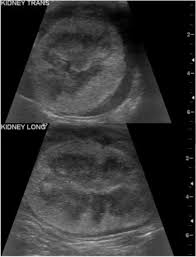

Feline kidney cancer is rare. Of the cancers that do develop in the kidneys lymphoma is the most common type to appear followed by renal cell carcinoma. Cats love routine so try to stick to a consistent feeding sleeping.

Kidney disease is divided into four stages with stage iv the most severe and most cats don t start showing clinical signs until stage iii.

Like other adenocarcinomas adenocarcinoma of the kidney is very aggressive growing rapidly and metastasizing to other parts and organs of the body. Your cat might benefit from dialysis if you afford it. Rare condition is cats that is usually associated with feline leukemia virus which is usually identified as the cause. This is not a common type of tumor in.